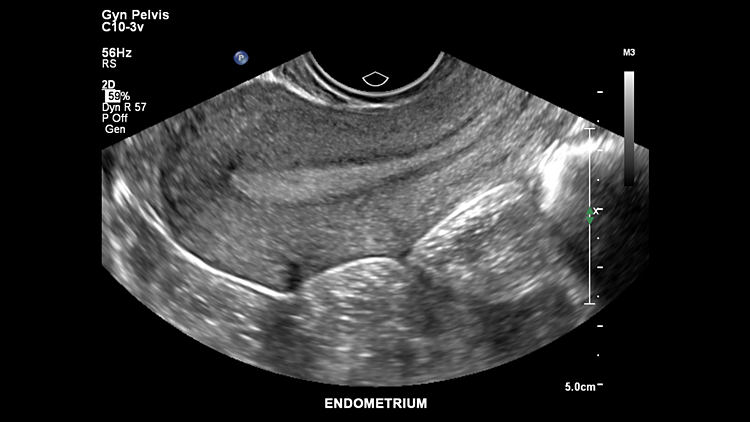

Слизистая оболочка матки, C10-3v

Фиброаденома матки, C10-3v

Фиброаденома матки, C10-3v